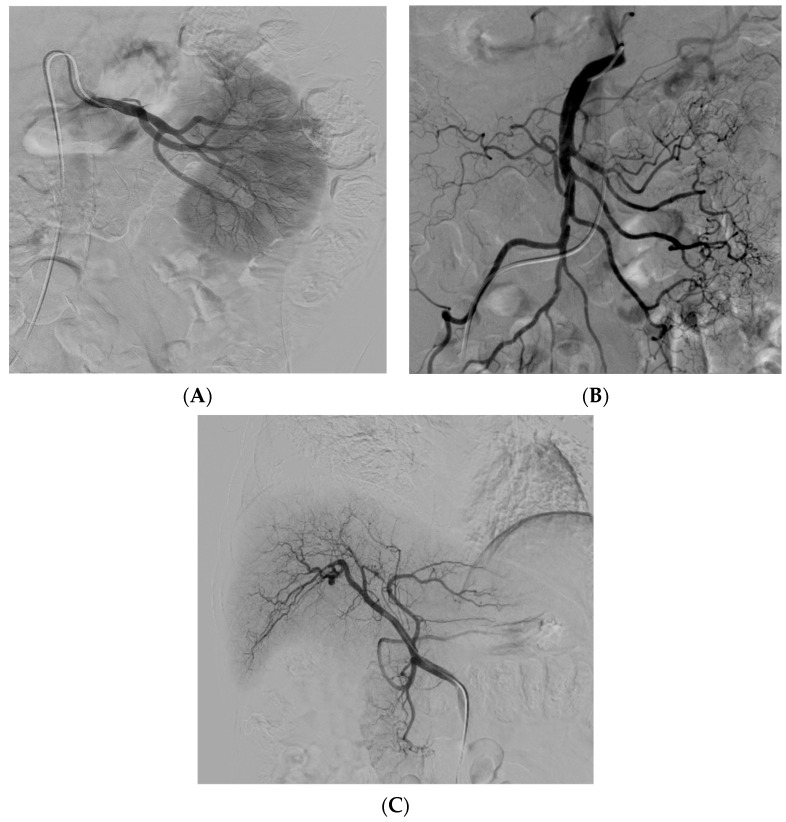

經(jīng)動(dòng)脈干細(xì)胞注射(TASI)可能被認(rèn)為是一種理想的選擇性遞送方法,在所需器官中具有最佳分布和高干細(xì)胞濃度。在組織取樣和干細(xì)胞分離處理(自體或異體)之后,該過程基本上包括通過動(dòng)脈通路(最常見的是股動(dòng)脈)引入導(dǎo)管。然后,在熒光鏡和造影劑引導(dǎo)下,將導(dǎo)管放置在所需的供血?jiǎng)用}(肝動(dòng)脈、腸系膜動(dòng)脈或腎動(dòng)脈)中,以進(jìn)行隨后的干細(xì)胞注射。圖2)。

導(dǎo)管定位確保對所需組織進(jìn)行選擇性治療,避免非目標(biāo)干細(xì)胞輸注。